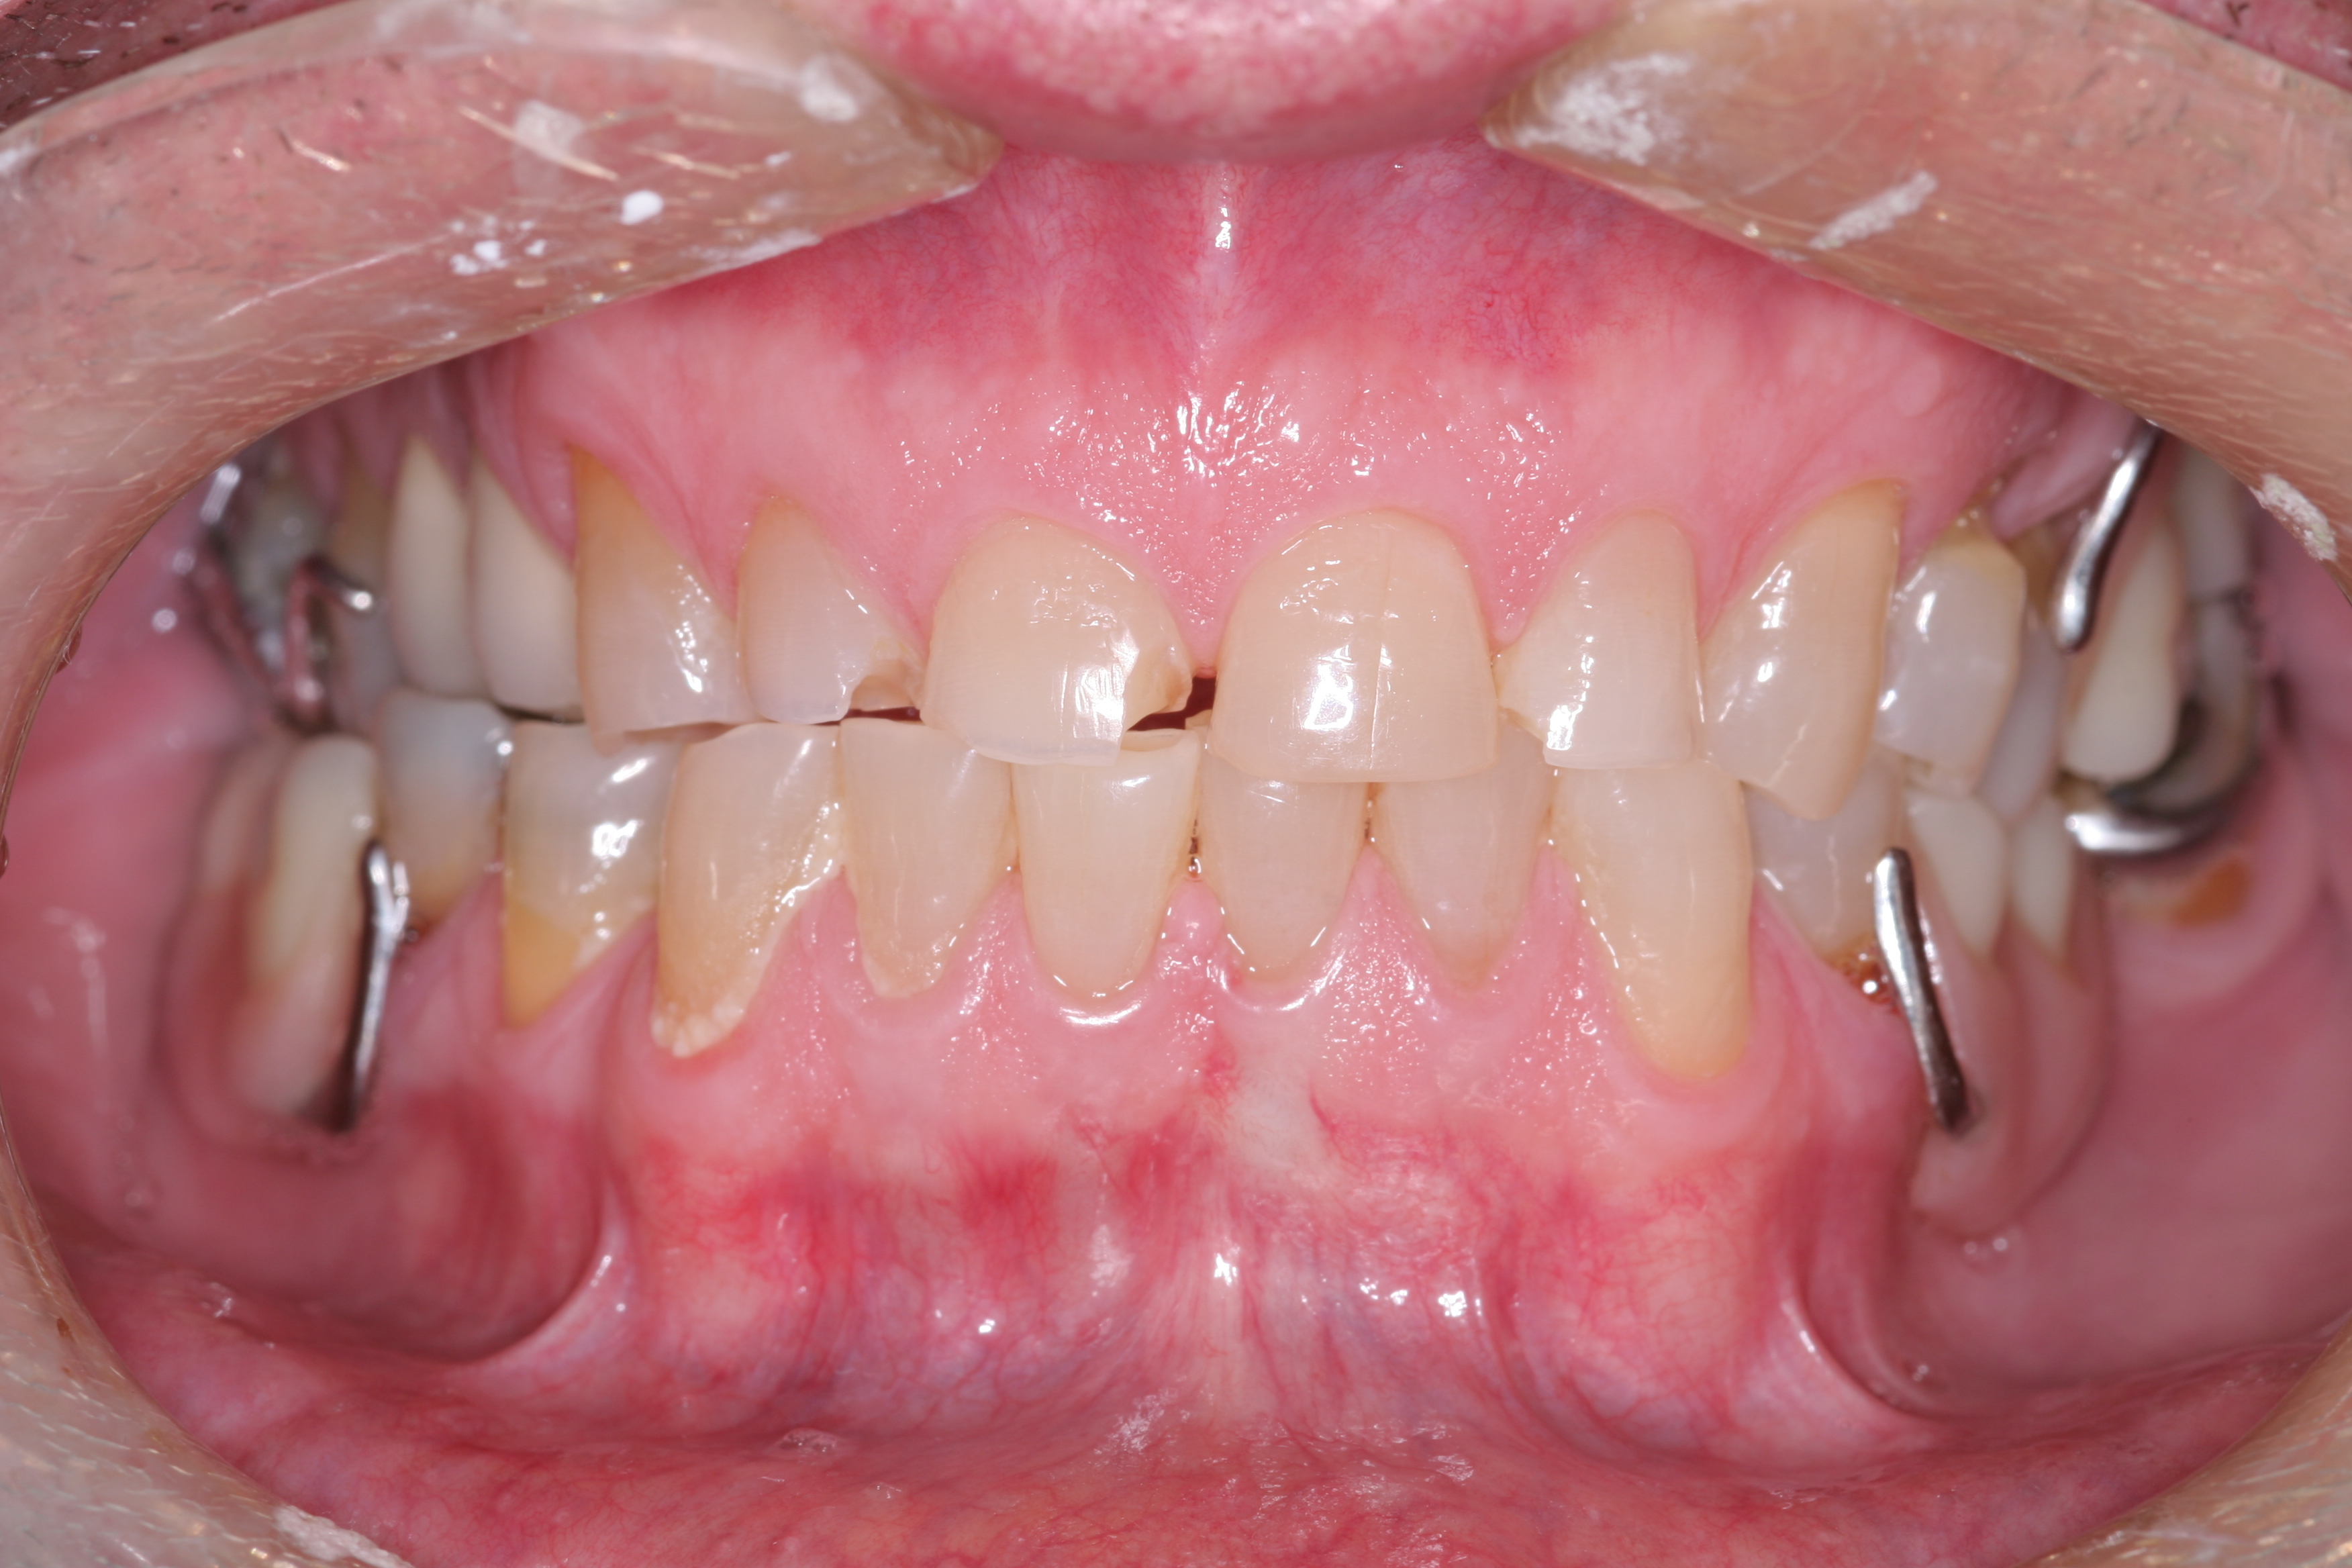

(10.) A patient presented with advanced generalized wear of her anterior teeth, and was displeased with their overall appearance because of their color and wear.

Figure 10

(11.) A patient presented with advanced generalized wear of her anterior teeth, and was displeased with their overall appearance because of their color and wear.

Figure 11

(12.) A patient presented with advanced generalized wear of her anterior teeth, and was displeased with their overall appearance because of their color and wear.

Figure 12

A patient presented with advanced generalized wear of her anterior teeth (Figure 10 and Figure 11). She was displeased with their overall appearance because of their color and wear (Figure 12). A complete examination was performed, revealing instability in her temporomandibular lateral poles bilaterally, sore muscles of mastication, advanced wear, a CR/MIP discrepancy, and loss of her anterior guidance due to the wear. Although the topic is beyond the scope of this article, the patient was also screened for possible sleep apnea. This included an evaluation of the Mallampati score, previous sleep therapy evaluation or treatment, snoring history, an evaluation of her neck size, her weight status, and the presence of the tonsils and their size. In every case, if this clinician suspects airway obstruction to be playing a role in tooth wear issues, the patient is referred to a sleep physician. The patient in this case displayed few apnea risk factors, and the patient’s anterior wear facets fit together like a “lock and key” pattern seen in parafunctional activity. Splint therapy was initiated to stabilize the joints and muscles. A repeatable CR position was verified through load testing. At this point diagnostic models, photographs, a CR bite record, and a facebow were taken and recorded.